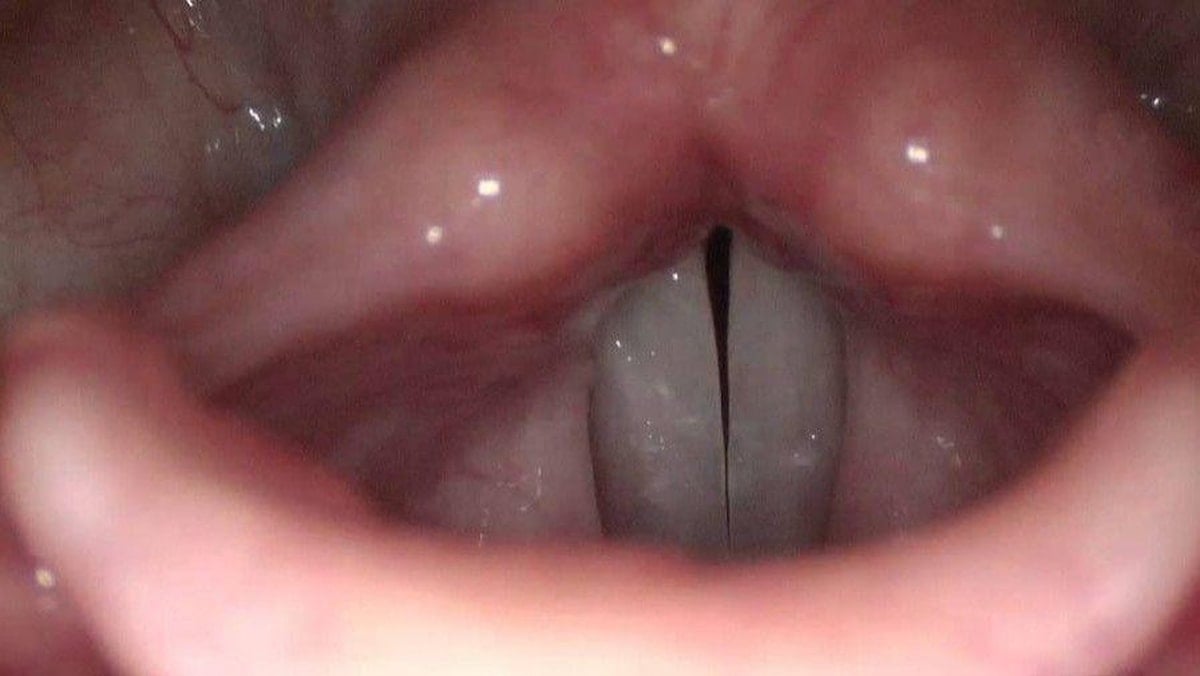

Ses telleri, boğazda gırtlak kısmında yer alır. Ses teli denilince gerçekten tele benzetenler olacaktır ancak görüntüsü oldukça farklı.

Sesimizin çıkmasını sağlayan ses tellerini gören şaşkınlık yaşıyor.

Peki siz hiç merak ettiniz mi? Bakın ses telleri nasıl görünüyor...

Gırtlakta yer alan ses telleri, hem sağ hem sol taraftan, oldukça ince bir ciltle sarmalanmış, kas lifleri ve yumuşak doku içeren oluşumlardır. Zarımsı bir yapıdadır.